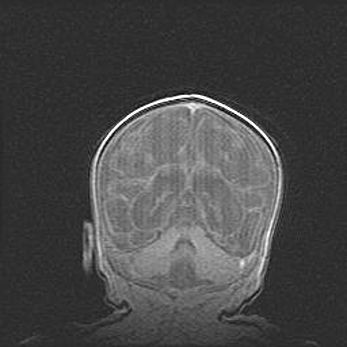

Наружная гидроцефалия с возможной атрофией височных областей.

Возраст: 28 дней

Вес: 3670 г

Пол: мужской

Окружность головы: 38 см

Срок гестации: 40 недель

Гидроцефалия головного мозга у новорожденных – это заболевание, которое характеризуется скоплением избыточного количества спинномозговой жидкости в желудочковой системе головного мозга в результате затруднения её перемещения от места выработки к месту поглощения в кровеносную систему или вследствие нарушения абсорбции. При открытой наружной форме гидроцефалии у новорожденных расширяются и переполняются субарахноидные пространства.

При нормотензивных  формах,  которые,  как  правило,  являются  следствием  перенесенных ишемических  повреждений  паренхимы  мозга,  возможно  сочетание микроцефалии  с нормотензивной гидроцефалией. В основе данных изменений лежит атрофия больших полушарий с преимущественной  локализацией  в  лобно-височных  областях.